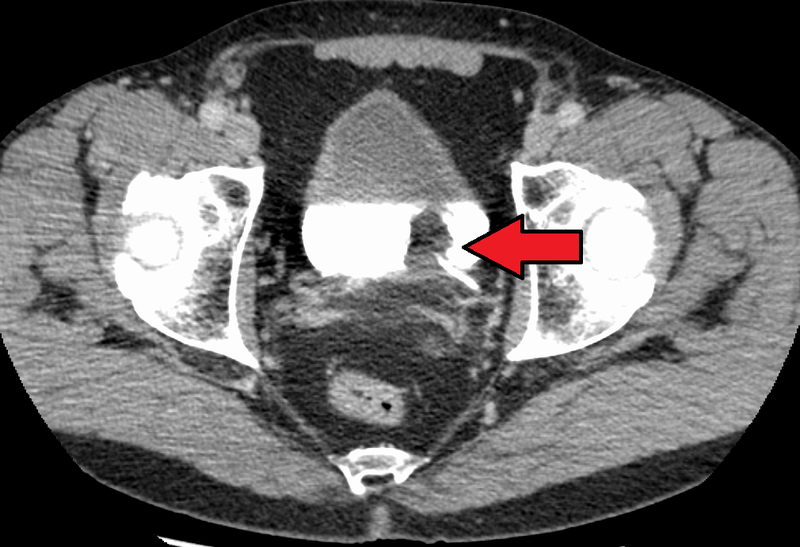

Renal Cell Carcinoma (RCC)

Renal cell carcinoma (RCC) is a malignant cancer cells are located in the lining of kidney tubules, which are incredibly tiny tubes. This condition is known as renal cell carcinoma.

Symptoms of renal cell carcinoma include:

- Hematuria (most common)

- Palpable mass

- Flank pain

- Fever

- Weight loss

- Paraneoplastic issues

Rarely, renal cell carcinoma may present with a left-sided varicocele.

The left spermatic vein cannot drain properly due to cancer in the left renal vein, which causes a varicocele.

Right-sided varicocele is not seen because the right spermatic vein empties straight into the inferior vena cava (IVC).

When examined under a microscope, the most common variant of renal cell carcinoma shows clear cytoplasm or a clear cell type.

Loss of the tumor suppressor gene VHL causes an increase in the growth-promoting hormone IGF-1 and the transcription factor HIF, which in turn causes an increase in the growth hormones VEGF and PDGF.

Renal cell carcinomas (RCCs) may be hereditary or sporadic.

Risk factors for sporadic renal cell carcinoma (RCC) includes:

- Male

- Age of 60 or older

- Smoking

Hereditary renal cell carcinomas (RCCs) typically develop in younger adults and are bilateral.

The autosomal dominant illness known as von Hippel-Lindau disease increases the risk of renal cell carcinoma (RCC) and cerebellar hemangioblastoma by inactivating the VHL gene.